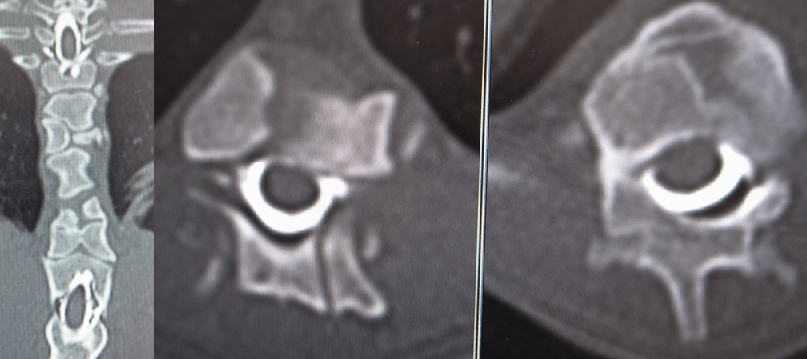

DLSSの手術で減圧だけやなくて椎間孔狭窄しないように椎体固定する事が若い大型犬とかで多いのですが…そのスクリュー刺すためのパイロットホール作って脊柱管にいってないかの確認CT

背中の骨のカタチ見ただけで犬種が判ってしまうやつ……。フレブルの困った後肢(不全)麻痺。若いフレブルで後肢の不全麻痺で椎体の奇形があってミエロCTで造影剤の入り悪ければ思い切って手術するのが良いと感じています。手術内容もおもいっきり振り切ってます(笑)5~6椎間ぐらいでドーサルラミネクトミーして椎体固定します。はっきり言える事は、胸腰椎脊髄障害グレードⅡぐらいで手術しないと手遅れになりがちです。もう一つはっきり言える事はリハビリにずっと通わされてるのはどーなん?…(汗

椎弓切除は絶対関節突起残す方の型で。幅広くやりすぎると良いように錯覚しますが変に肉芽みたいになります。椎体奇形で椎弓根(ペディクル)かなりわかりにくいので、感覚で刺すしかないような気がしてます。困らせてくるキュートな犬種、それがフレブル。